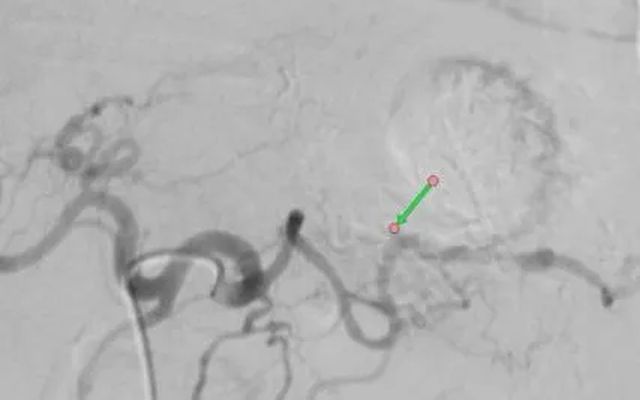

Dưới hướng dẫn của hệ thống chụp mạch DSA, ekip đã chọn lọc đến nhánh động mạch nuôi khối u và tiến hành tắc hoàn toàn nhánh mạch này nhằm chặn nguồn chảy máu. Sau thủ thuật, bệnh nhân được theo dõi sát. Sau ba ngày, phân đã chuyển vàng trở lại và chỉ số hemoglobin tăng dần từ 3,3 g/dL lên 7,7 g/dL.